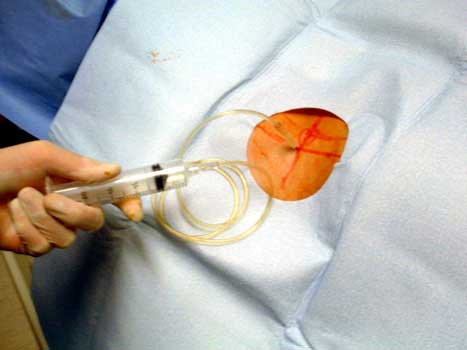

Sterile prep and drape

ARTHROGRAPHY

Needle advanced to metal

Aspiration of joint fluid

Aerobic and anaerobic culture tubes